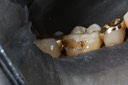

Russ Tabata #30 pre-op

Russ Tabata #30 buccal pre-op

Russ Tabata #30 amalgam removal

Russ Tabata #30 prep